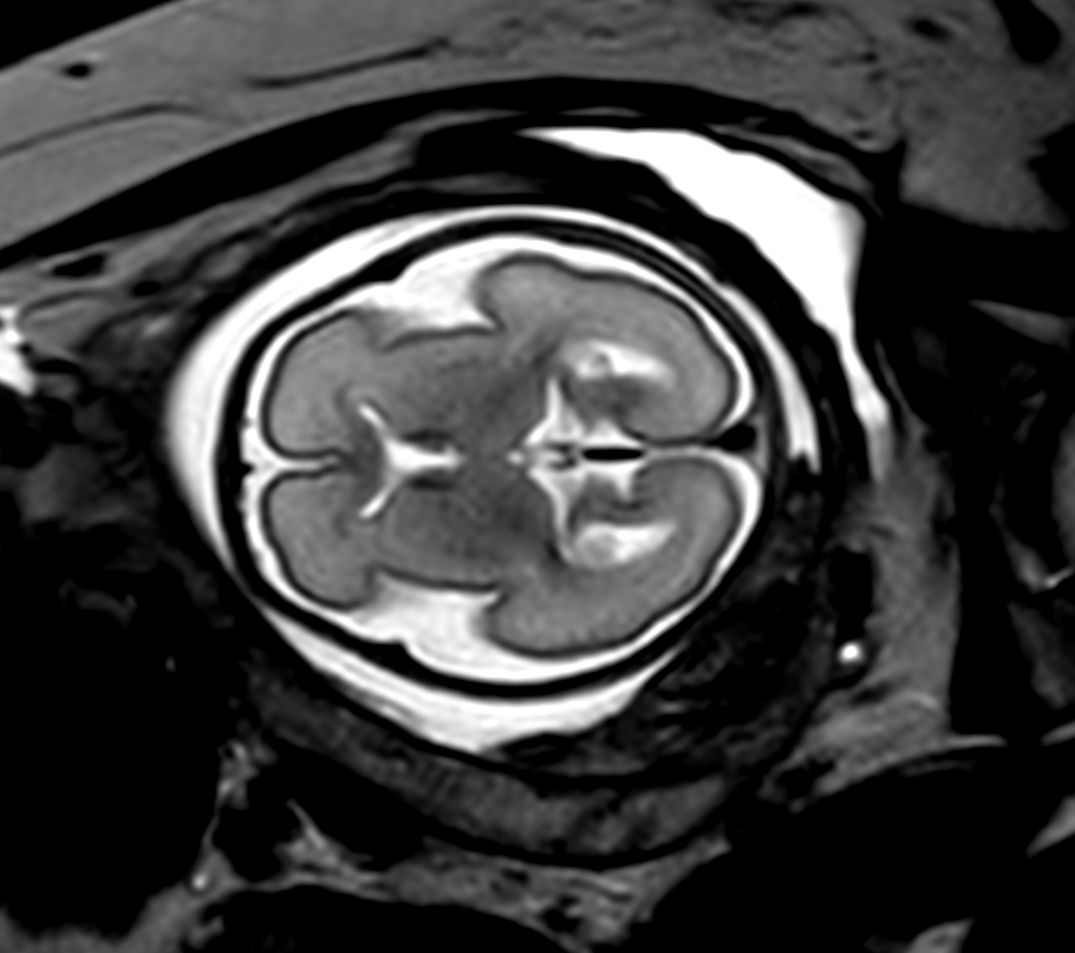

Pregnant patient, referred to MRI for fetal brain and spine imaging.

Coronal T2w TSE single shotCompressed SENSE